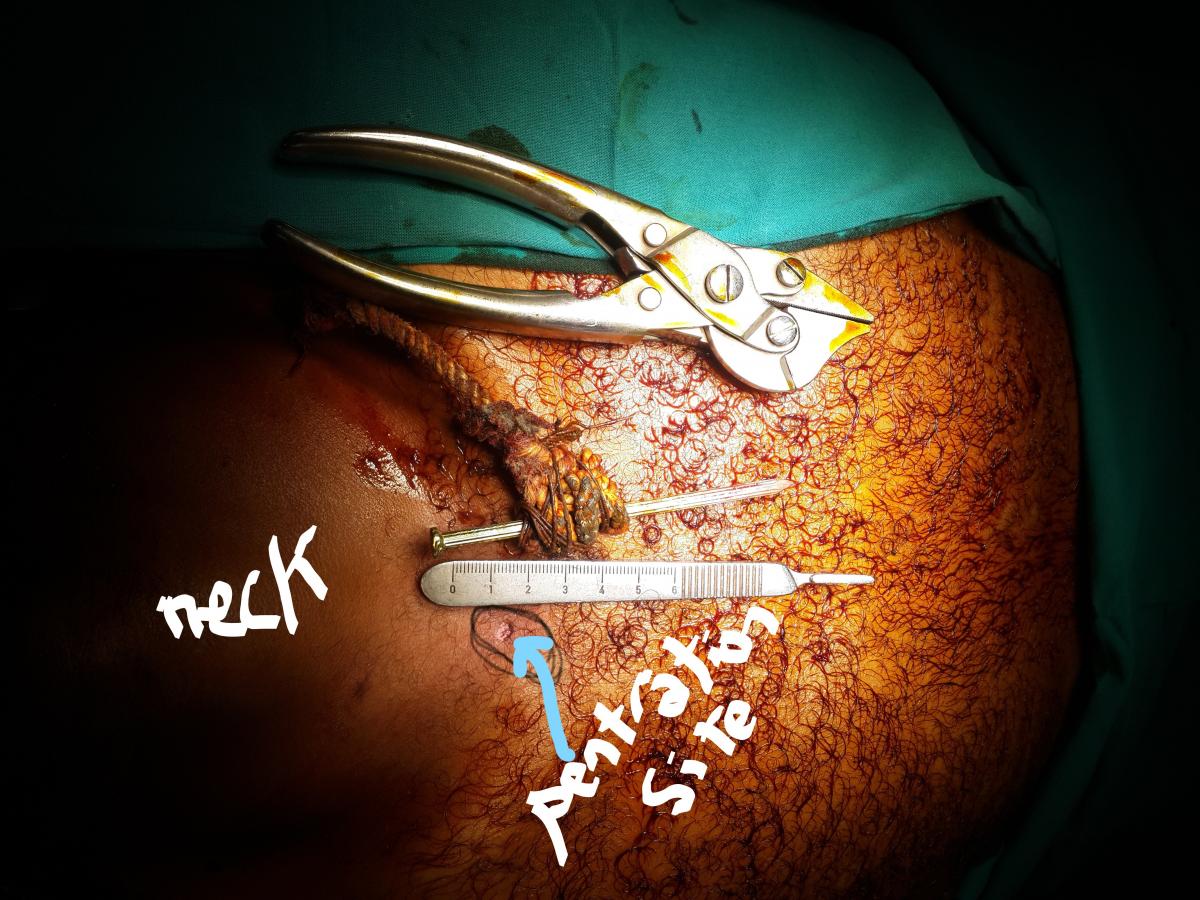

Figure 4. Illustration of the penetration site. The size of the nail is 10 cm. No bleeding from the penetration site.

The authors brought the patient to the operation room, as all physical findings and CT findings ruled out the presence of any cardiovascular or tracheal injury as the few millimeters penetration into the superior mediastinum was not enough to result in an internal injury. In the operation room, with the patient under general anesthesia without endotracheal intubation, the authors extracted the nail without exploration (Figure 3), although they were ready to explore if the indication arose. The extraction went smoothly and was uneventful with no bleeding (Figure 4). The total length of the nail was 10 cm. A follow-up CT was performed, and the patient was kept under observation for 24 hours and then discharged home.

In the authors’ opinion, the variability of the effect of the injury is related to many factors: the length and thickness of the nail, the direction of penetration, the power of the firing gun and its distance from the victim, time lag from the accident to hospital presentation, hospital facilities, and the wise management of the patient from the time of accident until hospital arrival. In this situation (Figure 1), we noticed a rope fixed around the nail that was related to a failed attempt by the patient’s relatives to extract the nail by pulling on the rope at the scene of the accident. In fact, the relative’s trial is very risky and should not be done.